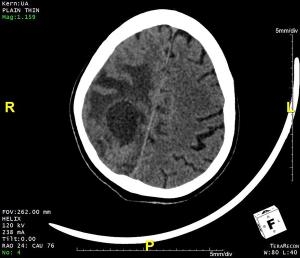

48-year-old female presented with complaint of seizures.